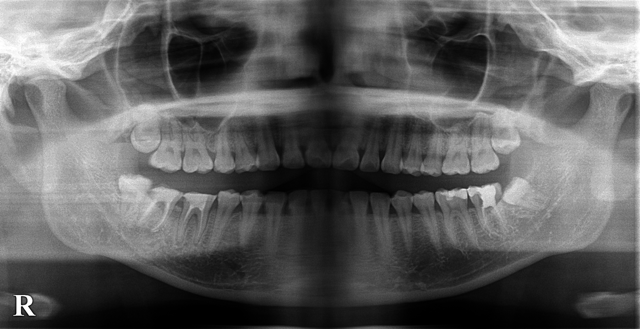

これは右下6が歯根破折して他院で抜歯といわれインプラントを勧められた症例です。

当院の診断でも抜歯後インプラントが一番ベターな方法だと思い、説明させていただきましたが

やはり費用、自分の歯で噛みたいという希望が強かったので歯牙移植術をしてみました。

今後は根っこの治療を行い、もし生着するようであればまた報告したいと思います!